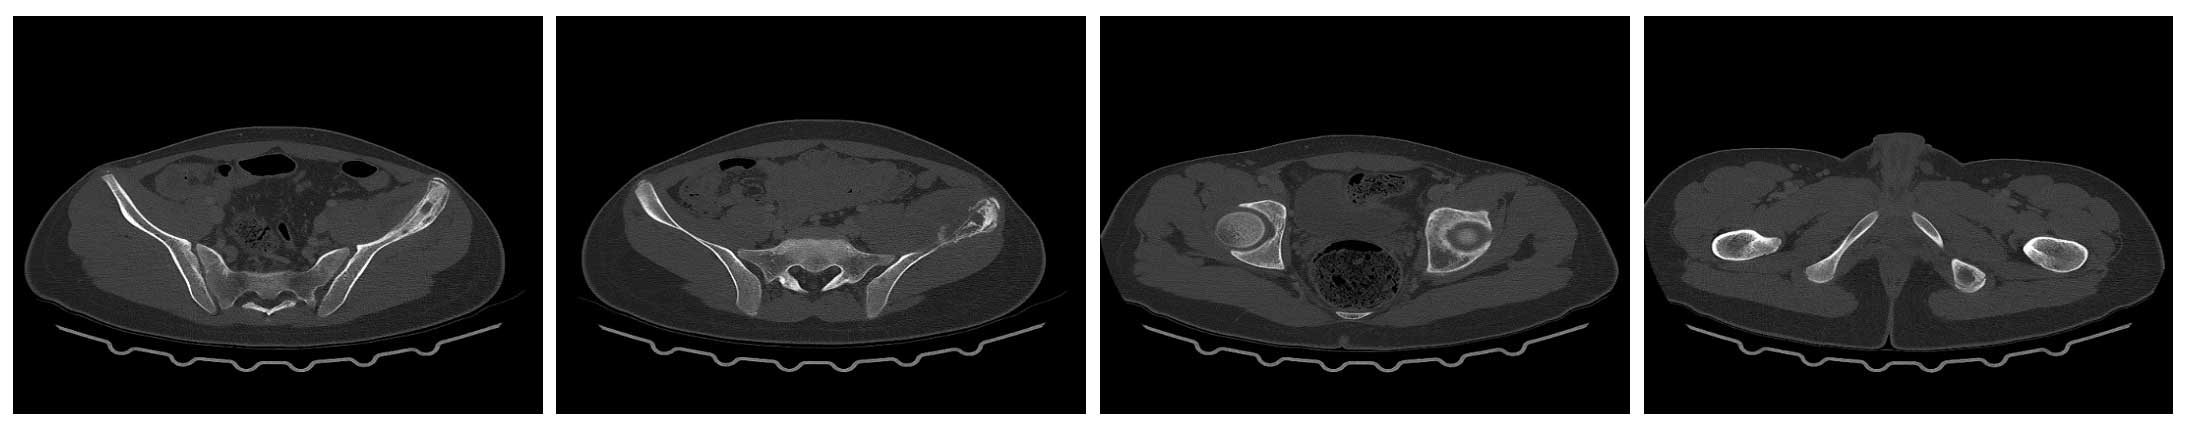

Ameliyat Öncesi: Sol iliak kanat üzerinde düzensizlik görülmekte.

Ameliyat Öncesi: Tomografide periost reaksiyonu ve harabiyet görülmekte.